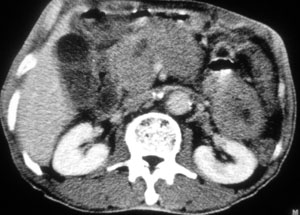

以下是引用liaoqiang在2008-6-13 15:20:00的发言:[br]1胰头区域肿块,胰管和胆管轻度扩张。肿块包绕肠系膜上静脉。考虑胰头癌可能性大。2胃底部壁增厚。

以下是引用liaizhi在2008-6-13 16:15:00的发言:[br]考虑胰头癌可能性大(胰头增大,胆囊增大,胰尾部及胆总管扩张.)胃大弯部胃壁增厚.胃占位?